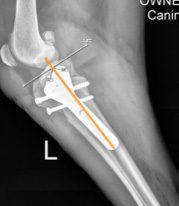

- In both CBLO and TPLO surgeries, a cut is made in the tibia. With a CBLO, the center of force that is placed on the stifle is positioned so that it is directly over the center of the tibia.(see image below). Conversely, the TPLO can cause the center of force to be over the posterior (back) aspect of the bone. In extreme cases, the center of weight can even be behind the bone. This often referred to as a “balcony effect”. This causes a functional limb deformity and can significantly alter the mechanics of the joint. (see image below)

An example of a CBLO where the center of weight (orange line) is in alignment with the center of the bone.

(Images complements of Hulse 2017)